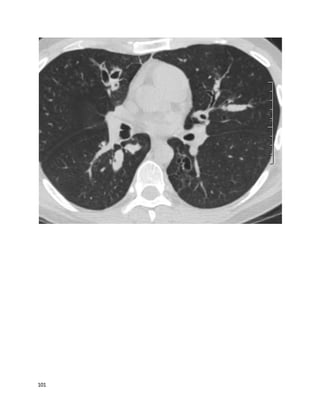

This 49 year old U.S. citizen originally from Trinidad is referred to you for

evaluation by her oncologist. She had the below chest X-ray after a mammogram

suggested abnormal lung parenchyma. Breast biopsy showed ductal carcinoma in

situ. She is to have lumpectomy soon. She has been mildly short of breath since her

20s, which has insidiously gotten worse, although she still works full-time and

takes care of 3 children. She also has a chronic dry cough worse on deep

20

inspiration. She has never sought evaluation for her symptoms and has never had

prior chest imaging. In your office, she walks 1000 feet in 6 minutes, with

desaturation from 100% on ambient air to 85% on ambulation with mild dyspnea.

A TB skin test is placed. An HIV test was negative last year.

PFTs:TLC 70% predicted (below lower limit of normal), FEV1/FVC ratio 0.65,

FEV1 2.1L (below lower limit of normal) DLCO 40% predicted, DLCO/VA 80%

predicted.

21

22

Without any other information, her most likely diagnosis is:

A. Idiopathic pulmonary fibrosis

B. Sarcoidosis

C. Tuberculosis

D. Lymphangitic spread of breast cancer

We feelthat B is the best answer.

Sarcoidosis is more prevalent in people of African descent, and can present at a

young age and progress insidiously. This woman likely has diffuse lung fibrosis

without hilar lymphadenopathy, so-called stage IV sarcoid. The term "stage"

misleadingly implies a predictable pattern of linear disease progression; in fact, the

radiographic pattern (stage) correlates neither with chronicity nor with changes in

pulmonary function.

Although patients usually have restrictive lung disease at presentation, as many as

50% also have obstructive disease. Bronchodilator responsiveness is not

uncommon. Spirometry returns to normal in 80% of patients within 2 years (with

about 67% of patients achieving a complete remission of sarcoid within 10 years).

Sarcoidosis is a diagnosis of exclusion, with a minimum requirement of a biopsy

demonstrating noncaseating granulomas (except in certain patients, such as those

with Lofgren's syndrome, Heerfordt's syndrome, or asymptomatic, incidentally

discovered hilar lymphadenopathy). At that point, other granulomatous diseases

must be excluded. This patient had a noncaseating granuloma on breast biopsy --

which can also be seen in breast cancer and which therefore still left some

diagnostic uncertainty. Her symptoms and imaging have been stable over years

since her first visit; she remained in remission from breast cancer after

lumpectomy and radiation.

Miliary TB would be expected to producea more nodular pattern on chest films, as

opposedto this linear or reticular pattern. In situ cancer would not likely have

spread lymphangitically. IPF usually preferentially affects the peripheral and basal

lungs. The small nodule in the right lung baseis probably of no significance.